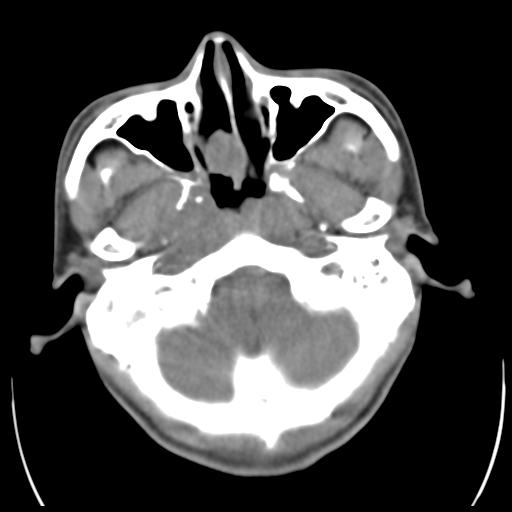

35m 鼻子时不时流血,头及右侧面部痛,颈部淋巴结未见明显大

软组织窗

考虑鼻咽癌侵犯颅底并突入右侧鼻腔;双侧中耳乳突炎。

蝶窦,后组筛窦及鼻咽部团块状软组织影,骨壁破坏,病变较广泛。考虑恶性肉芽肿。建议活检。

颅底骨质明显破坏 支持鼻咽癌 但病灶的边缘毛糙 不能除外炎性